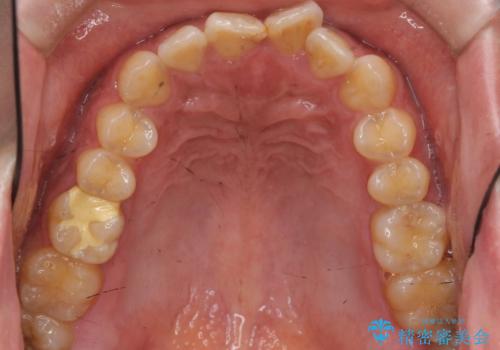

前歯のねじれを 1年かけずに矯正 インビザライン

- 前歯のねじれを主訴に来院。

インビザラインで治療しました。

前歯のねじれをセラミックで治そうとすると、抜髄といって、神経の治療が必要になる上、歯の幅も制限が出て理想的にはなりません。

保定の必要がありますが、天然歯を並べる矯正治療では、治療後の心配事が非常に少なく、保存的な処置となります。